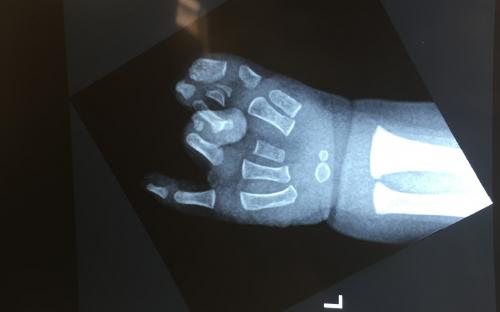

Παιδί με σύνθετη πλήρη συνδακτυλία του αντίχειρα, του δείκτη και του μέσου, στην οποία συμμετείχε μερικώς και ο παράμεσος. Αντιμετωπίστηκε με διαχωρισμό του αντίχειρα και απελευθέρωση της εγγύς φαλαγγοφαλαγγικής άρθρωσης του παράμεσου σε ηλικία 9 μηνών.